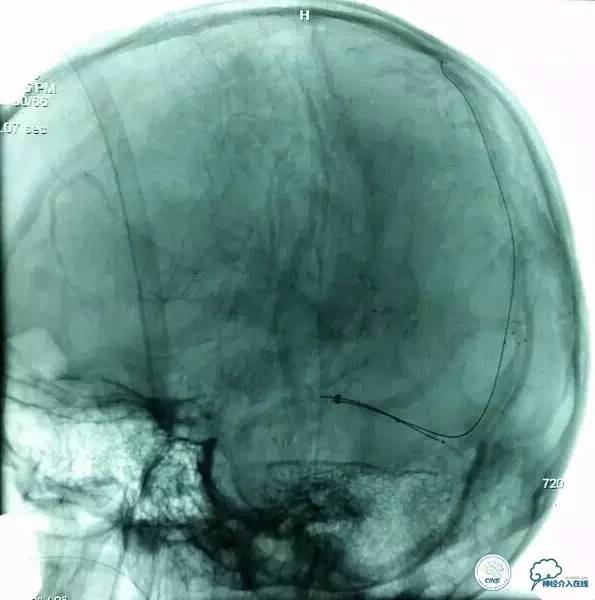

▼8F-Guiding 导管+6F-Navien 导管到位,微导丝选入上矢状位窦内。

▼Solitare6mm-30mm支架放于近端窦汇处,血栓中,5分钟后取栓。

▼取栓后再次,微导管到矢状窦: